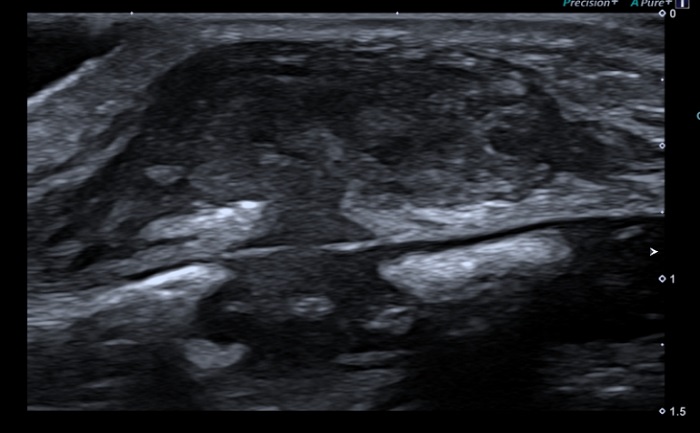

Lactante de 22 meses, con antecedente personal de asma en relación con procesos infecciosos, que acudió a su pediatra por aparición de tumoración, de manera súbita, en unión del tercio medio e inferior del esternón, sin otra sintomatología asociada. Negaba traumatismos previos o procesos infecciosos intercurrentes. En la exploración en consulta, presentaba una tumoración de consistencia dura de unos 0,7 mm de diámetro localizada en la unión del tercio medio e inferior del esternón, no dolorosa a la palpación, no adherida a planos profundos, sin signos flogóticos. El resto de la exploración física por aparatos no presentó otros hallazgos. En cuanto a las pruebas complementarias, mediante radiografía de tórax se descartó dependencia ósea; y mediante ecografía de partes blandas (Figura 1), se identificó una pseudocolección subcutánea de 10 x 18 x 23 mm de tamaño con morfología en reloj de arena que se extendía entre los centros de osificación del esternón paramedial izquierdo, en íntima relación con unión condrocostal vecina, con una ecoestructura heterogénea e hipoecogénica, sin aumento de la vascularización local ni cambios inflamatorios perilesionales. Ante los hallazgos clínicos y ecográficos compatibles con SELSTOC, se decidió una actitud expectante basada en controles ecográficos seriados mensuales. No se realizaron otras pruebas complementarias ni se administró ningún tratamiento. En las ecografías de control, se apreció una disminución del tamaño de la lesión hasta su completa desaparición, lo que apoya el diagnóstico de SELSTOC.

| Figura 1. Ecografía de partes blandas donde se objetiva imagen típica en “reloj de arena” de los SELSTOC |